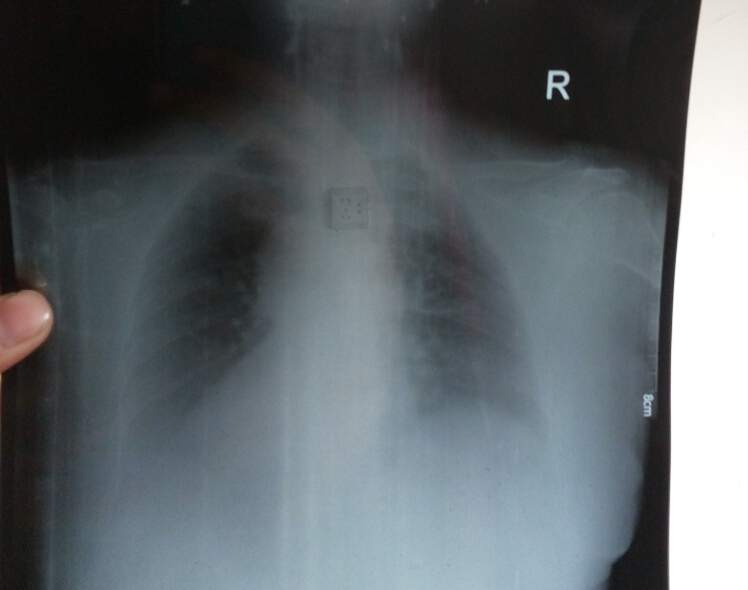

求详细分析两张体检单,金币不是问题哦 已有4人参与